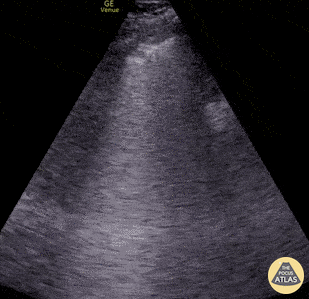

Seen here is an irregular and thickened pleural line with associated focal and confluent B lines in a patient with COVID-19 pneumonia. Edgar Miranda